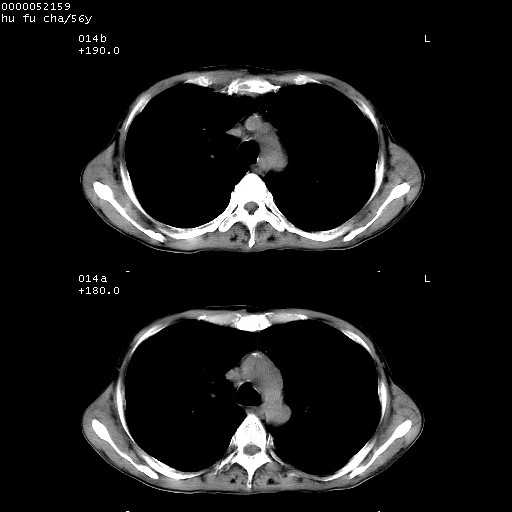

以下是引用zsl6918在2008-8-25 22:47:00的发言:[br]胸骨,胸椎及肋骨均可见多发转移表现,肝内低密度结节不除外转移。原发灶可能在右肺。双侧可见支扩表现。